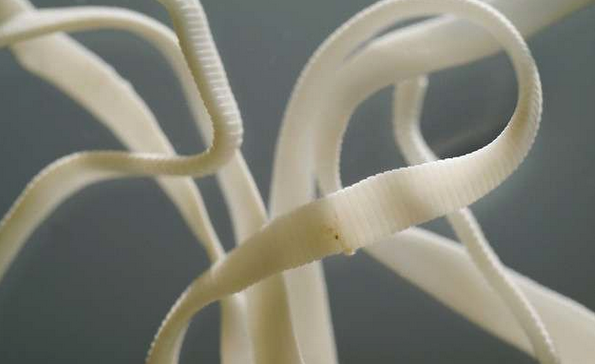

▼16. 人類體內發現過最長的條蟲達82英呎長…感覺可以做成義大利麵了。